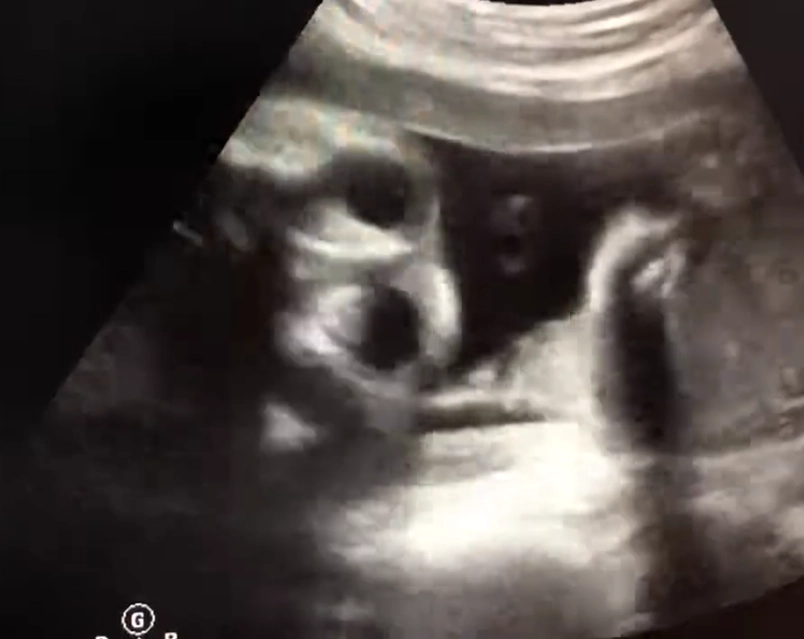

Tật hai mắt xa nhau thai nhi (Hypertelorism)